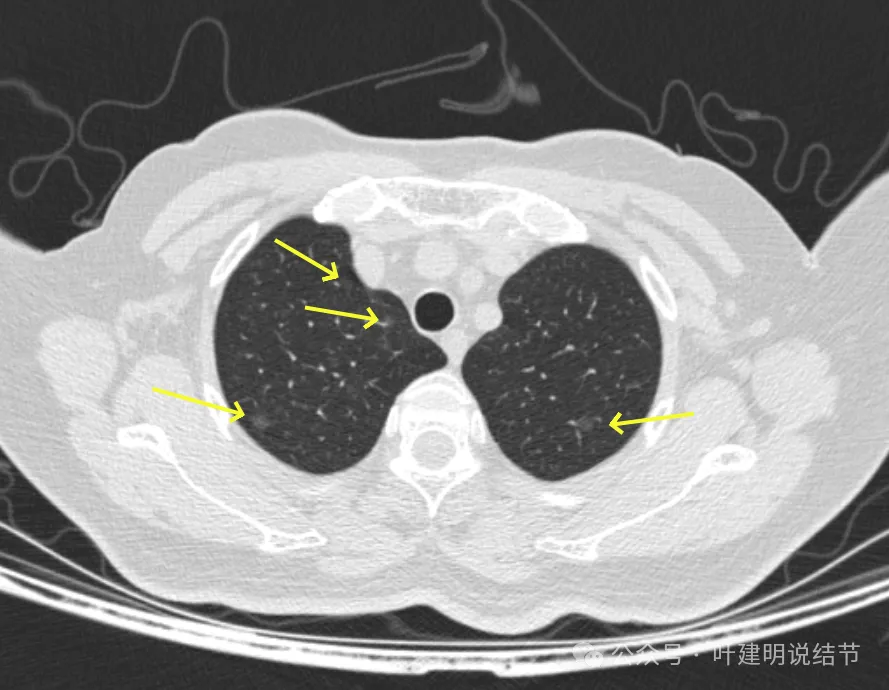

病灶1-4:两肺多处淡磨玻璃结节,密度低,散在,轮廓较清。

病灶11-14:两肺淡磨玻璃结节,轮廓较清。